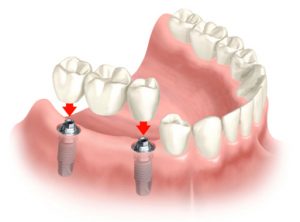

- Single dental implants: Ideal for replacing one or two missing teeth, consisting of individual implants with a crown.

- Implant-supported dental bridges: Recommended for multiple adjacent missing teeth, utilizing two implants to support the bridge securely.

- Implant-supported dentures: For cases of extensive tooth loss, 4-6 implants provide stability and support for dentures, preventing slipping and enhancing functionality.